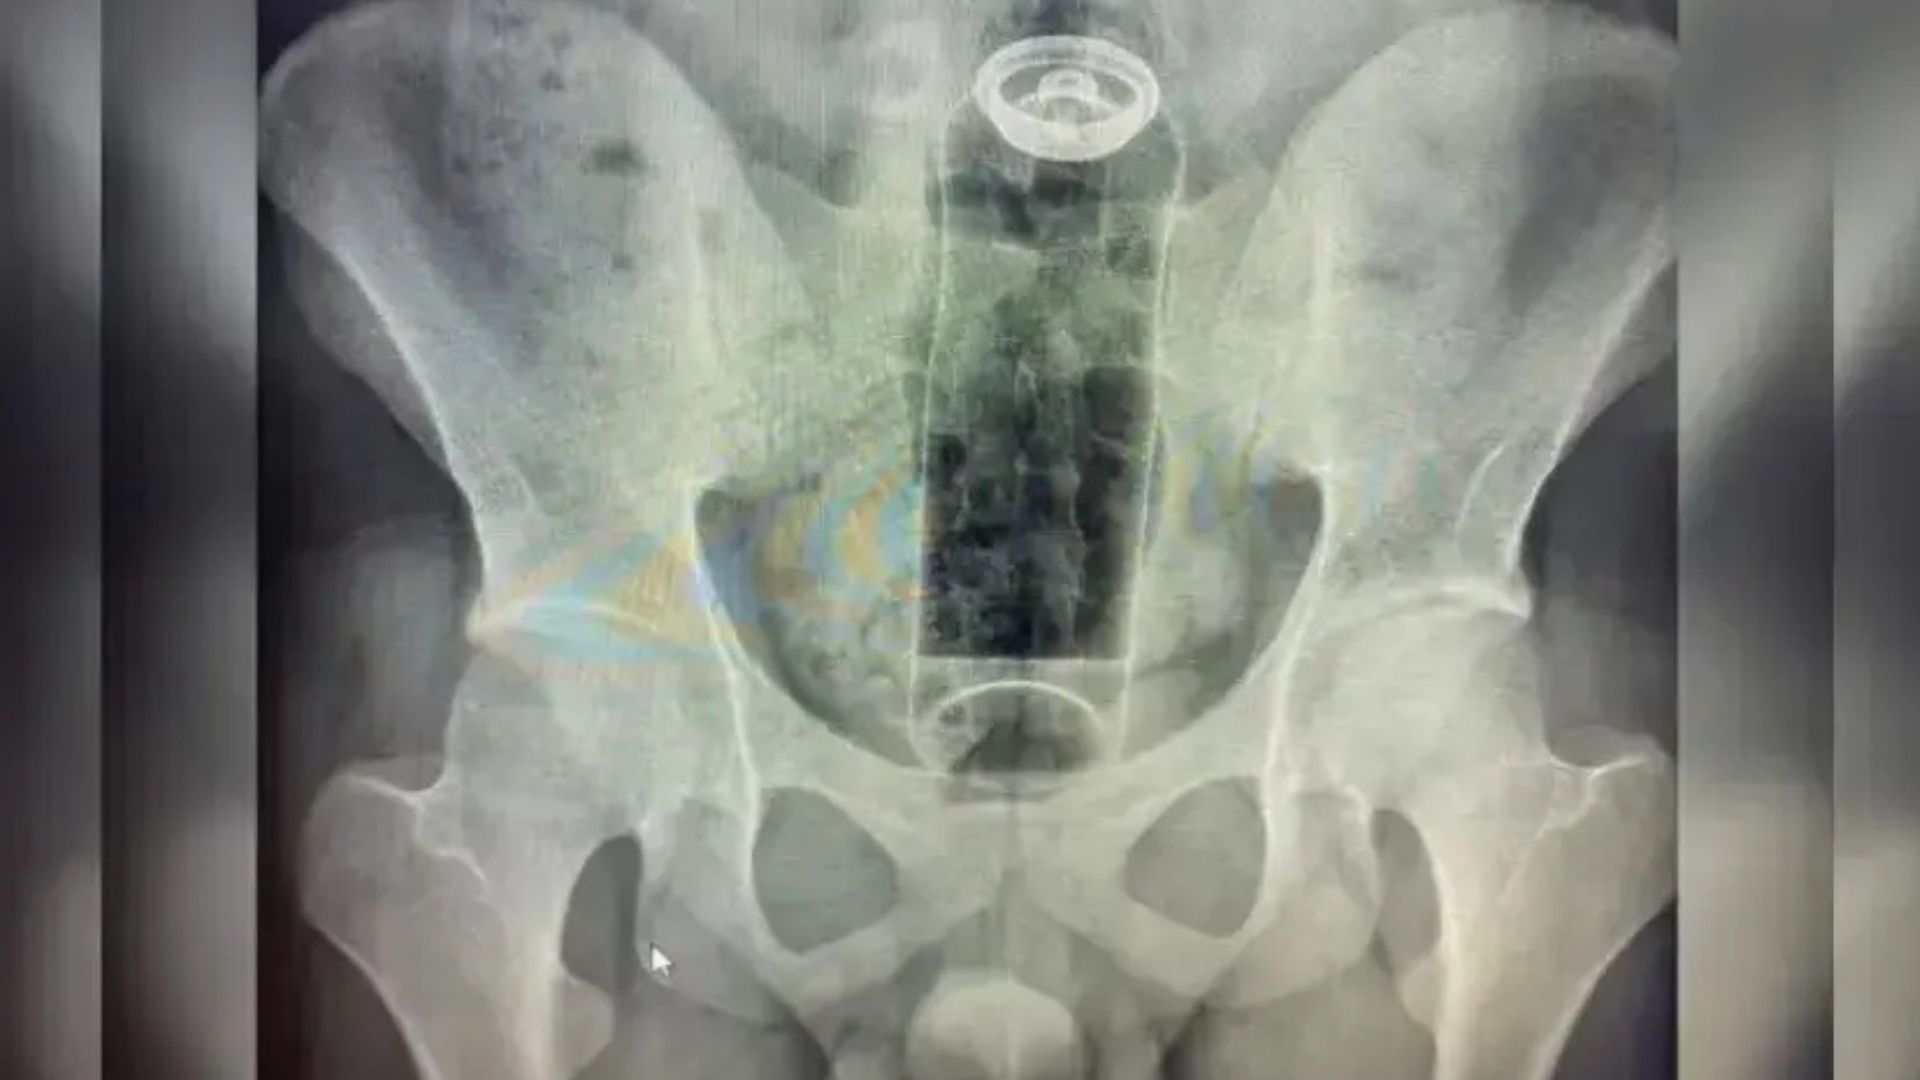

Um jovem de 19 anos precisou de atendimento hospitalar após um desodorante ficar alojado na região retal durante uma prática íntima. O caso exigiu intervenção médica especializada porque o objeto foi empurrado para o interior do intestino, o que inviabilizou a retirada por meios domésticos.

Após a intervenção, o paciente permaneceu em observação hospitalar. Posteriormente, ele recebeu alta médica sem registro de complicações graves. De acordo com os profissionais envolvidos no atendimento, a resposta rápida ao buscar ajuda contribuiu para um desfecho clínico favorável.